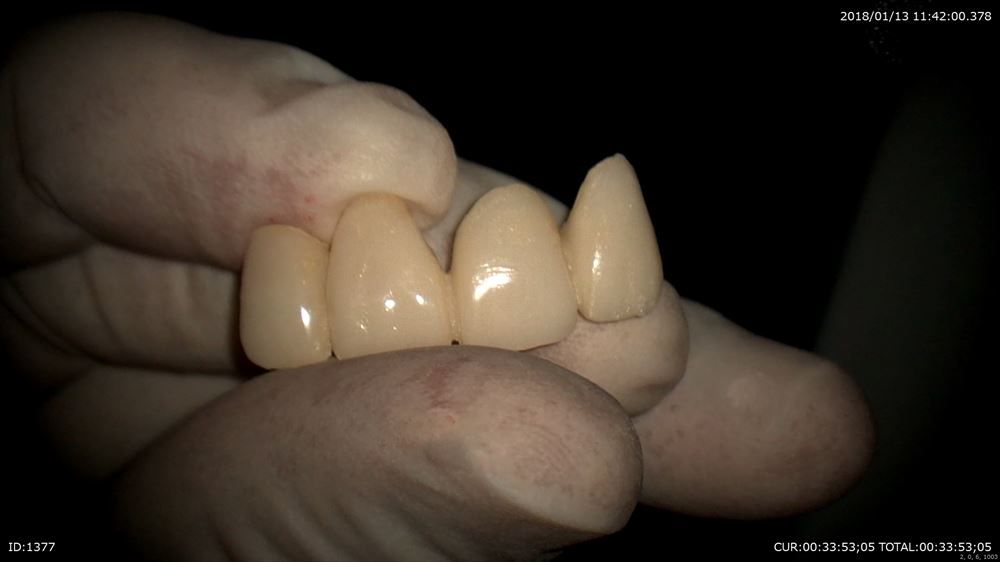

右上1番のインプラント歯茎の形態を仮歯で作ります。

マイクロスコープ治療で仮歯を調整。

エマージェンスプロファイルを調整。

仮歯完成!!インプラントの淵が見えなくなりました。あー緊張した。ここまで1年。患者さま喜んで頂けました。

ここからまた3ヶ月みて最終的な型をとります。前歯の治療ですので妥協は絶対ダメです。うちの技工士に怒られます。